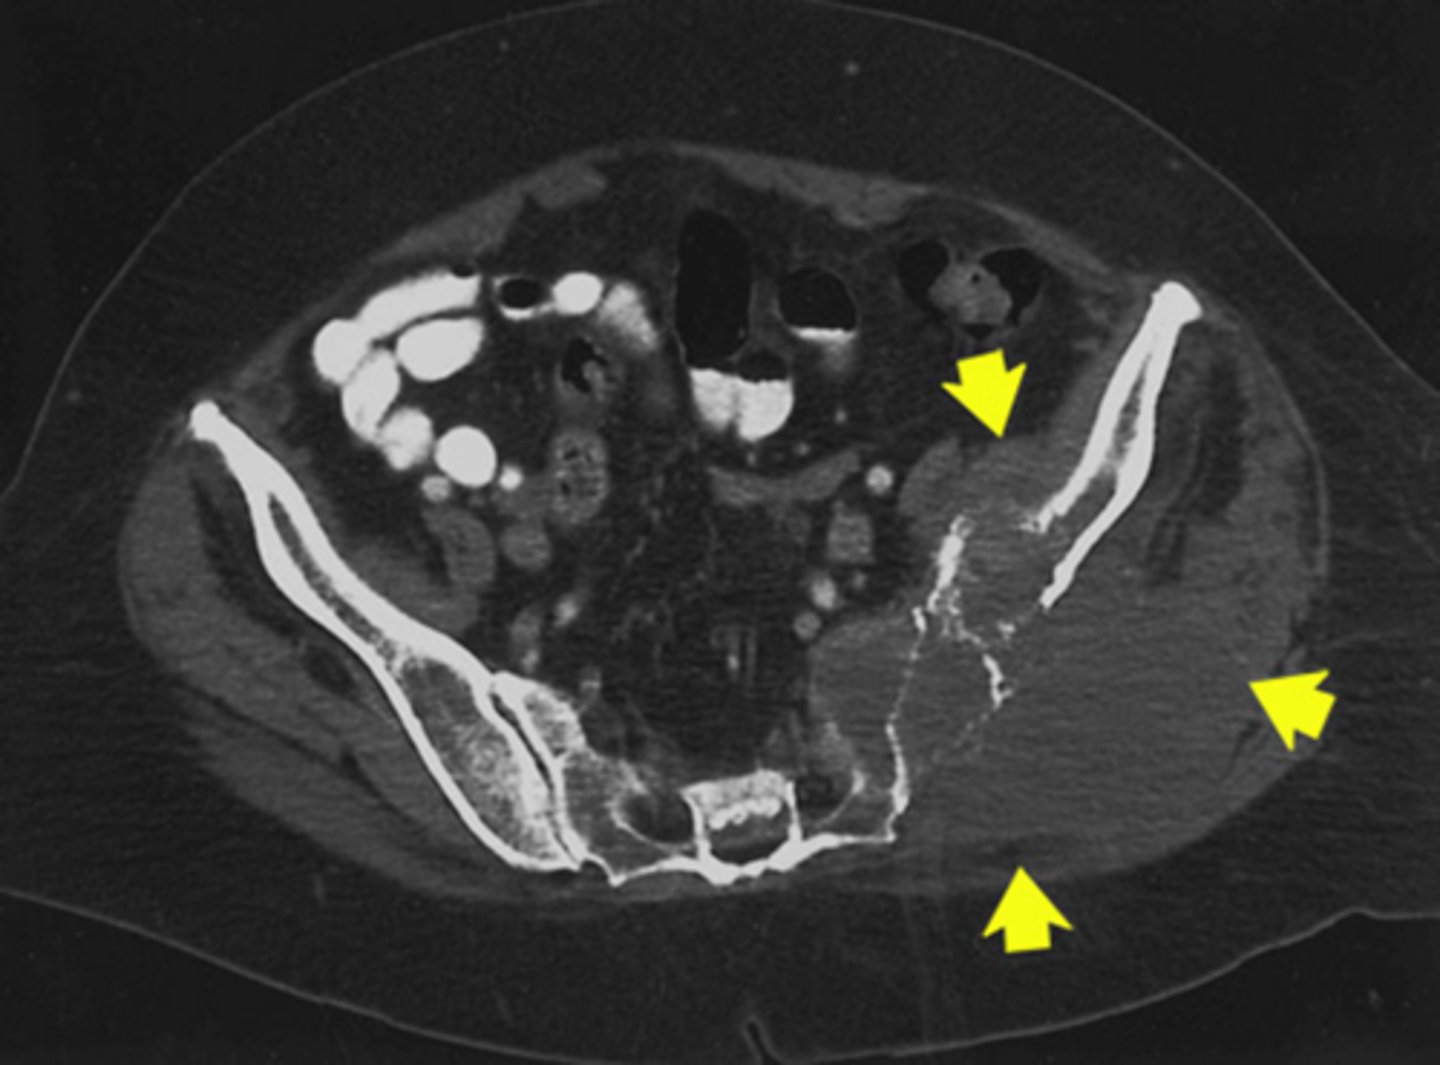

Colitis

What pathology is circled in blue

1) Left ilium

2) Left sacrum

Where is this pathology located (2)

Lytic (Destructive)

What type of pathology is this

1) Left pelvis

2) Left iliacus

3) Gluteus muscles

Where on the body is this pathology located (3)

Osteolytic (destructive)

What kind of pathology is this

Destructive

What kind of pathology is this